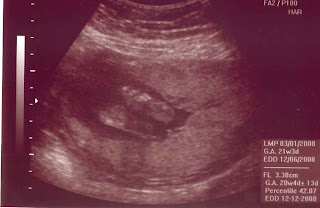

Well as you guessed from the heading, we are having a boy! He is going to be big boy and is weighing in at 15 oz:) Matt is really praying for a 6'5" left handed pitcher!

His weight is slightly above average for a baby at 20 weeks but as my cousins have reminded me, big babies run in the family. Even if they are born average, they grow quickly. We feel so blessed that baby is healthy and mama too! Thanks to all our friends and family that have kept us in your prayers.

Here are a few ultra sound photos, I can not really tell what is going on. For the photo shoot our lil' guy was sitting breach with his feet up near his head and for me it was difficult to tell what we were looking at. The ultrasound tech has being doing this for 20 years so I have confidence in her abilities.

Somewhere in here is a penis?

legs stretched out...but only for a minute!

Hand

Bottom of his feet